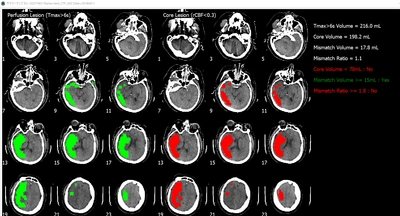

脳画像解析プログラム PMAneo 販売開始のお知らせ ~ 医療機関向けに新たな医療用画像解析ソフトウェアを販売 ~